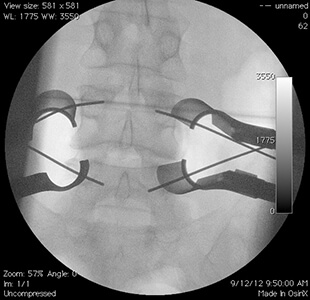

Διεγχειρητικές εικόνες επέμβασης ελάχιστα επεμβατικής δυναμικής σπονδυλοδεσίας σε ασθενή 45 ετών με χρόνια οσφυοισχιαλγία και υποτροπή δισκοκήλης στο Ο4/5